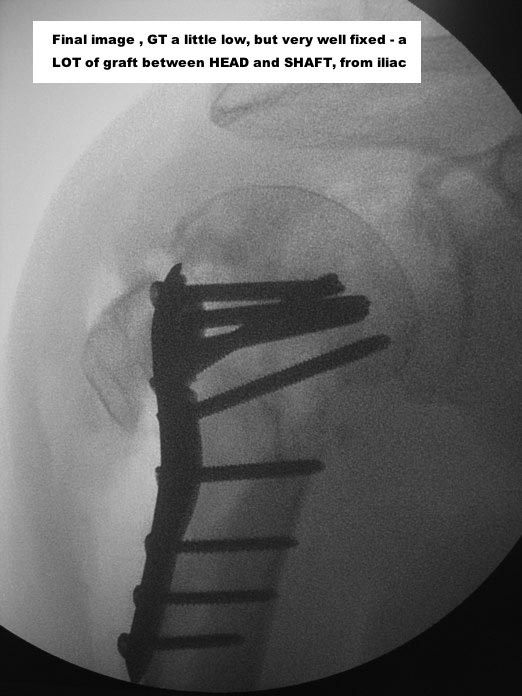

I would, for sure, use a tricortical iliac graft, between diaphysis and head

With a good PHILOS, surgeon must re-establish the best cephalic-diaphyseal angle (head-shaft relation) he can, and fix that

Here are some photos, of chronic, locked, 4 part posterior dislocation, 2 months old, that I did September/2011. Patient is 67, very, very active - had a really reasonable, honest clinical result ...

Photos attached ...